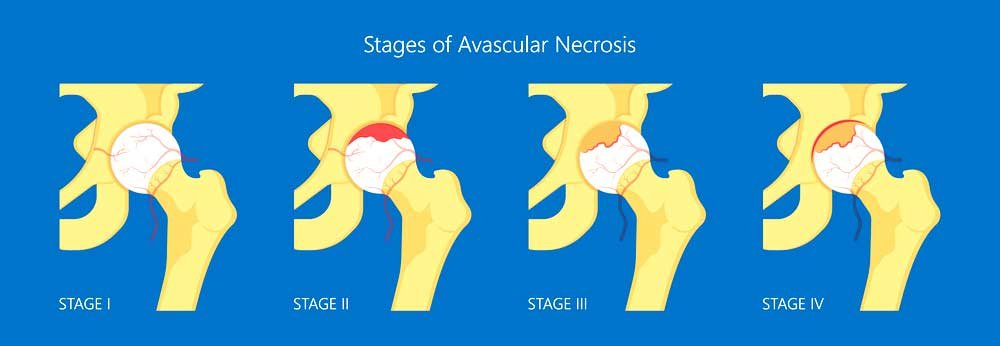

Image Source: https://manhattansportsdoc.com/hip-avascular-necrosis-avn-manhattan-new-york-city-ny/

In the starting stage, there are no symptoms of avascular necrosis. It may take weeks or months before you notice any symptoms. Some of the common signs that indicate avascular necrosis are:

- Minimal pain in the joint, especially when you put pressure on the bone

- Increasing joint pain and stiffness

- Limping if the knee or hip joint is affected

- Limited range of motion

- Difficulty in walking, standing, or climbing stairs

If the joint collapses, you will be in excruciating pain, due to which you will not be able to use your joint.